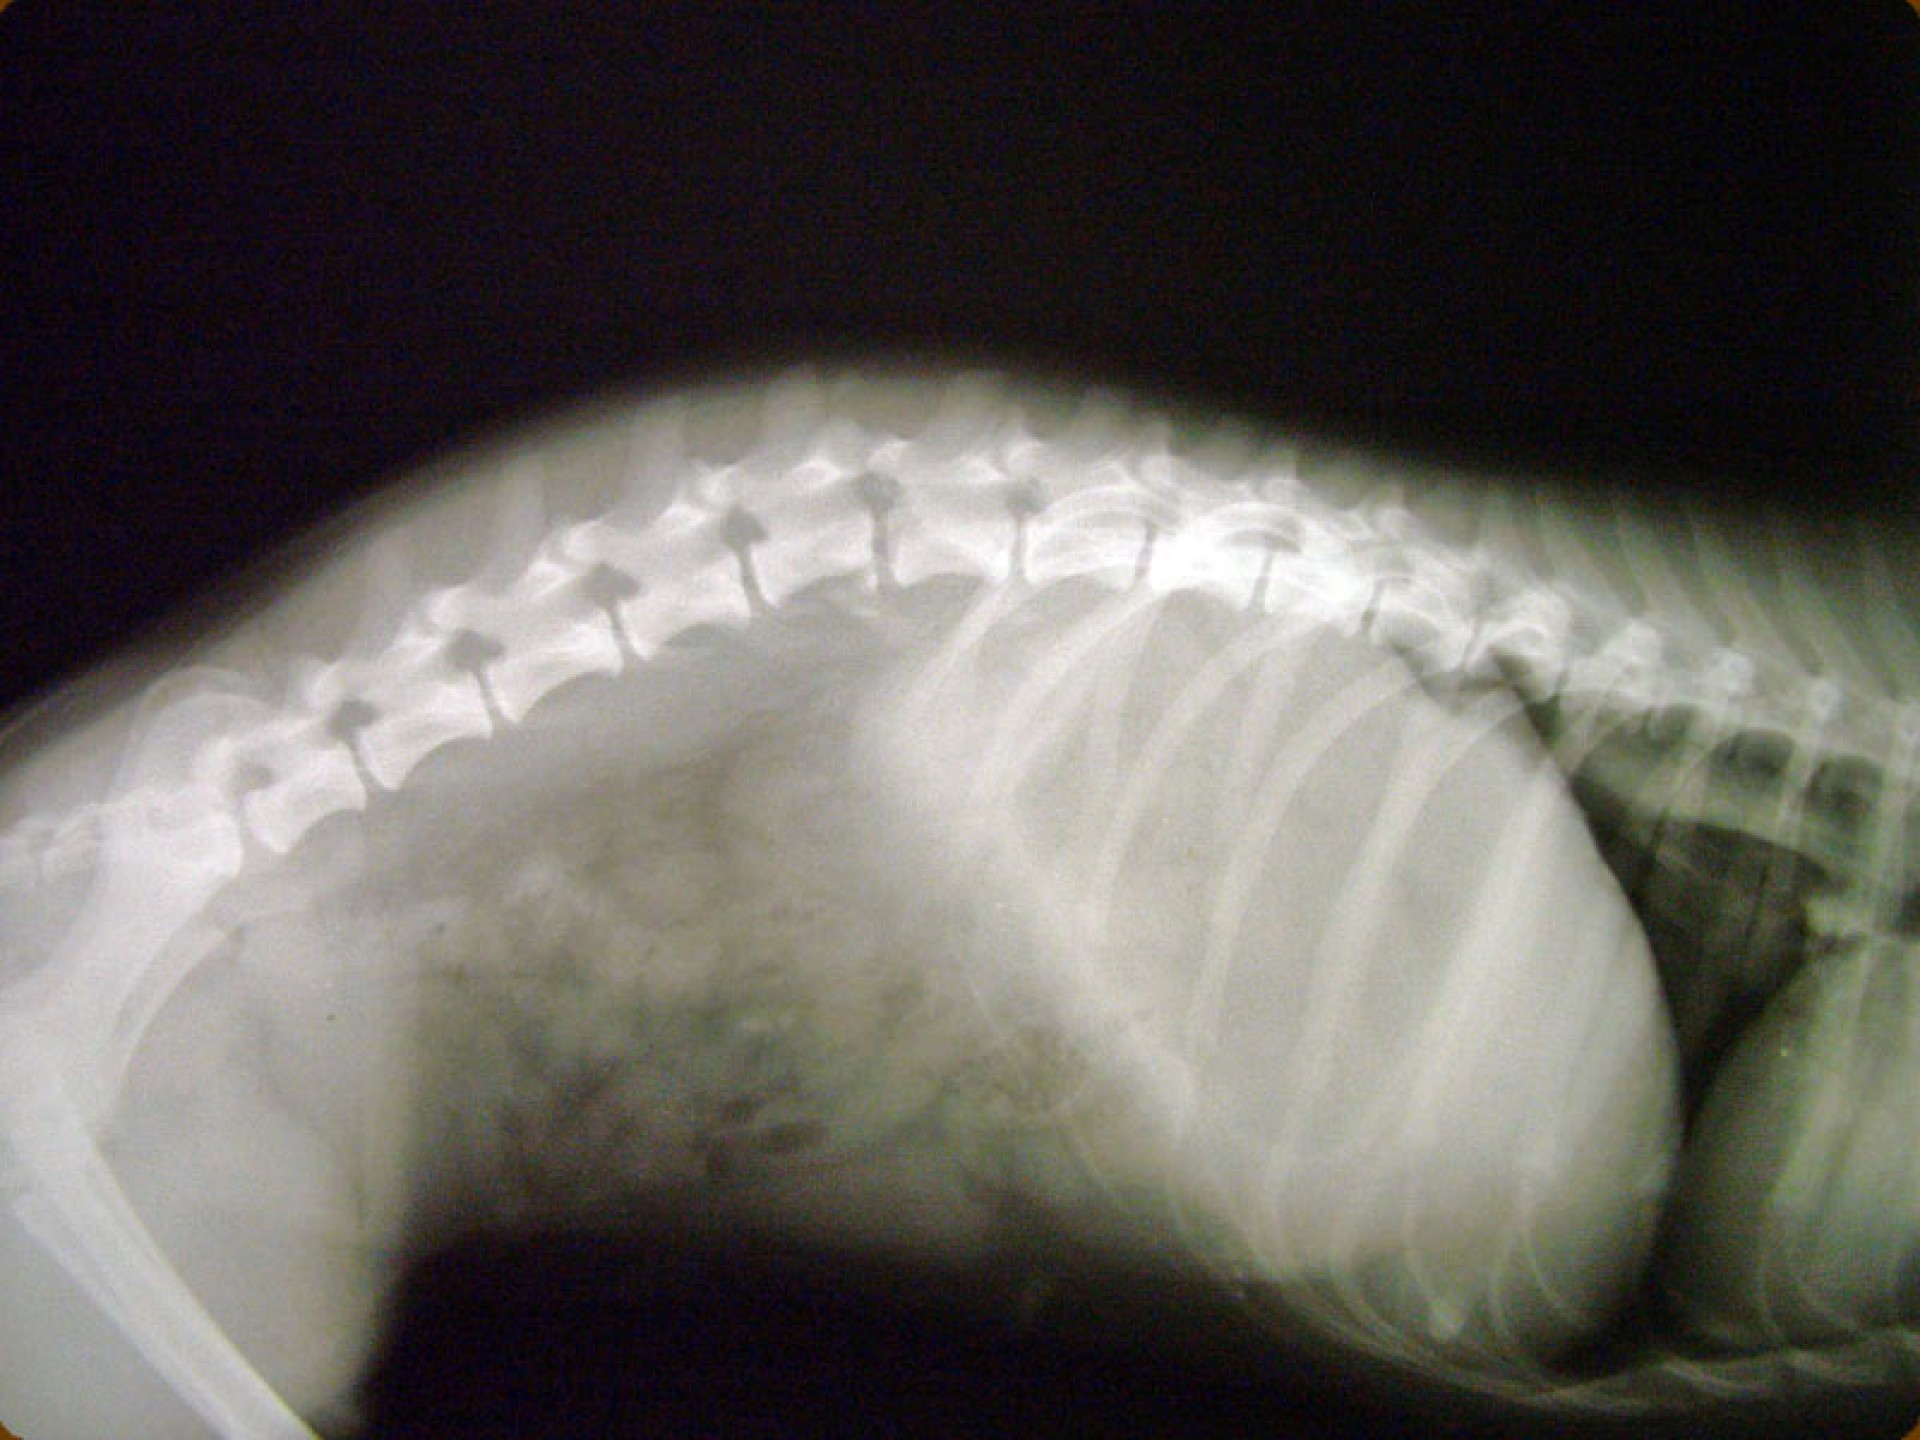

A gerinctörések műtéti ellátása kettős feladatot jelent: egyrészről a törés és elmozdulás következtében kialakult gerincvelő összenyomatást kell megszüntetni, másrészről a tört végeket kell adaptálni és eredeti állapotban - a további elmozdulás megakadályozása érdekében - rögzíteni. A műtéti ellátás során ezért minden esetben az érintett területen a gerinccsatorna felső csontos ívét eltávolítjuk (total laminectomia) így a gerincvelő sérülésének mértéke egyértelműen látható ill. a későbbi összenyomatása elkerülhető.

A törött csigolyatestek adaptációja és rögzítése a nyitott gerinccsatorna mellett komoly kihívást jelent. A későbbi elmozdulás elkerülésére többféle műtéttechnika alkalmazható, melyek közül a csigolyatestek lemezes osteosynthesise ill a fixateur interna használata terjedt el leginkább. Első esetben a sérülés előtti és mögötti csigolyákat lemez és csavarok segítségével egymáshoz rögzítjük, míg az utóbbi esetben a törés előtti és mögötti egy vagy több csigolyatestet két oldalról behelyezett csavarok és egy steril kétkomponensű akrilát műgyanta segítségével rögzítjük.